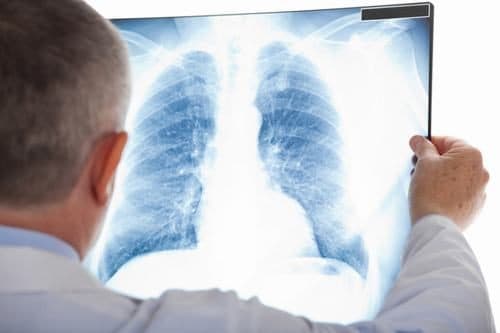

Chụp X quang phổi bao nhiêu tiền? Cần lưu ý những gì?

Chụp X quang phổi là một chẩn đoán hình ảnh quan trọng để chẩn đoán các bệnh lý về phổi. Vậy chụp X quang cùng phổi bao nhiêu tiền và cần lưu ý những gì? Bài viết dưới đây sẽ giúp bạn giải đáp cụ thể. 1. Vai trò chụp X quang trong chẩn đoán […]